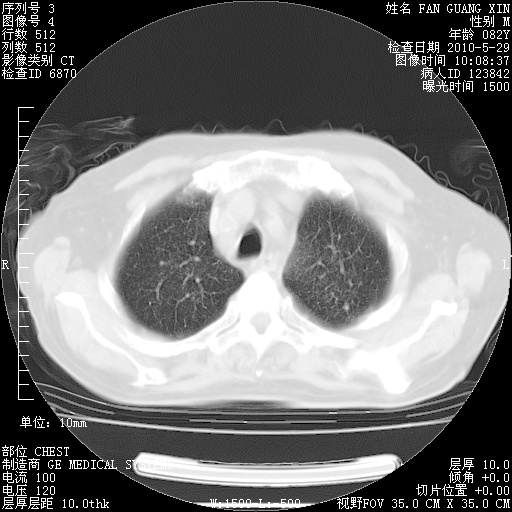

再治疗10天后的肺部CT

再治疗10天后的肺部CT 纵膈窗

肺部体征:呼吸25次/分,心率100次/分,呼吸音增粗。无干湿罗音。

从白细胞总数和中性比例看好像合并感染。肺部纹理好像比上次多,支气管炎?其他感染?

阅读此次胸部CT,肺间质渗出性改变较入院时有吸收。目前从体温、白细胞、中性分叶明显增高,肯定存在细菌感染(发生医院感染哦,若无消化道及泌尿系统等感染的依据,肺部感染可能大)。若你院头孢哌酮舒巴坦钠耐药率较高,同意你的方案,若48小时体温仍高,可考虑使用碳青霉稀类抗菌药物,同时可予超声雾化、注意滴数时加大液体量。白蛋白33.30g/L较低哦,需加强营养等支持治疗。